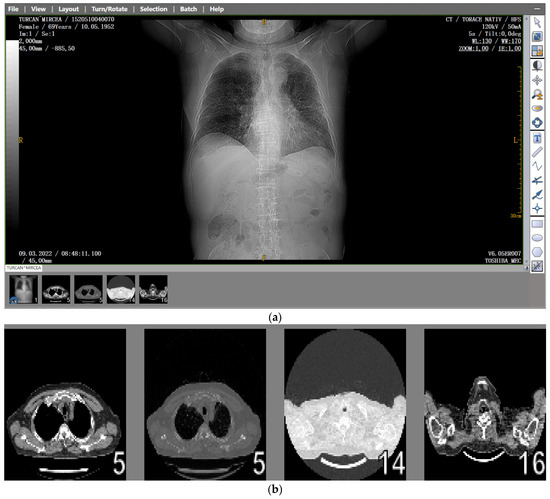

Several patients with a preliminary diagnosis of COVID-19 were tested using CT imaging with the contrast substance OMNIPAQUE 350. The pulmonary CT images obtained for each patient, along with their detailed fractal analysis, are presented in Figure 1, below.

The chest radiograph of healthy lungs on which the fractal analysis was performed is shown in Figure 29a. Aside from the high-quality imaging provided by CT procedures (Figure 29a,b), the picture evaluation assured quantitative information regarding various structural features, such as the fractal dimension and lacunarity.

Figure 1. (a) The CT scan image of a 69-year-old patient who underwent a chest CT examination due to suspicion of COVID-19 in the lungs. (b) A schematic representation of the pre-processing phases of the patient’s CT image (2D), which was resampled to an isomorphic resolution. The indices 5, 14, and 16 represent the numbers of the slices in order.